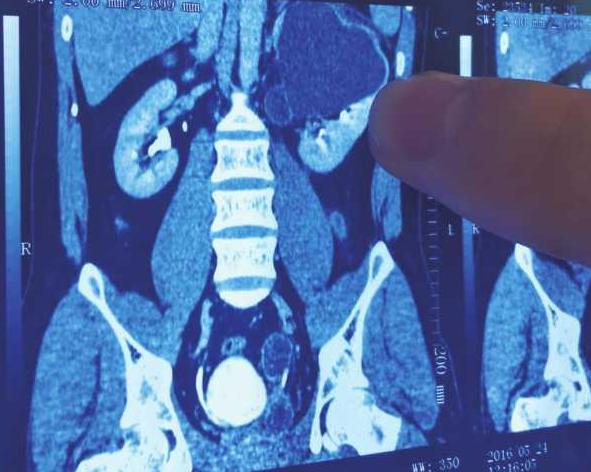

虽然雷先生一直坚持是因为结婚后发福了,可在家人的一再催促下,他还是来到了医院检查,医生在给雷先生的大肚子做了彩超后,大吃一惊,虽然雷先生的肝脏和胃都正常,但是他竟然有4个肾脏!

雷先生的右侧一个肾脏的输尿管没有接入膀胱,呈闭锁状态,这就造成了大量的尿液在输尿管里聚积,如果一旦发生破裂导致感染,严重的会危及生命。

上图中左侧是正常人的腹腔,右侧是雷先生的腹腔,图中可以看出,其腹腔2/3的空间被肿大的输尿管占满,形成了囊肿,随时可能破裂,所以医生决定,迅速对雷先生进行手术,切除右侧重复肾脏和病变的输尿管。